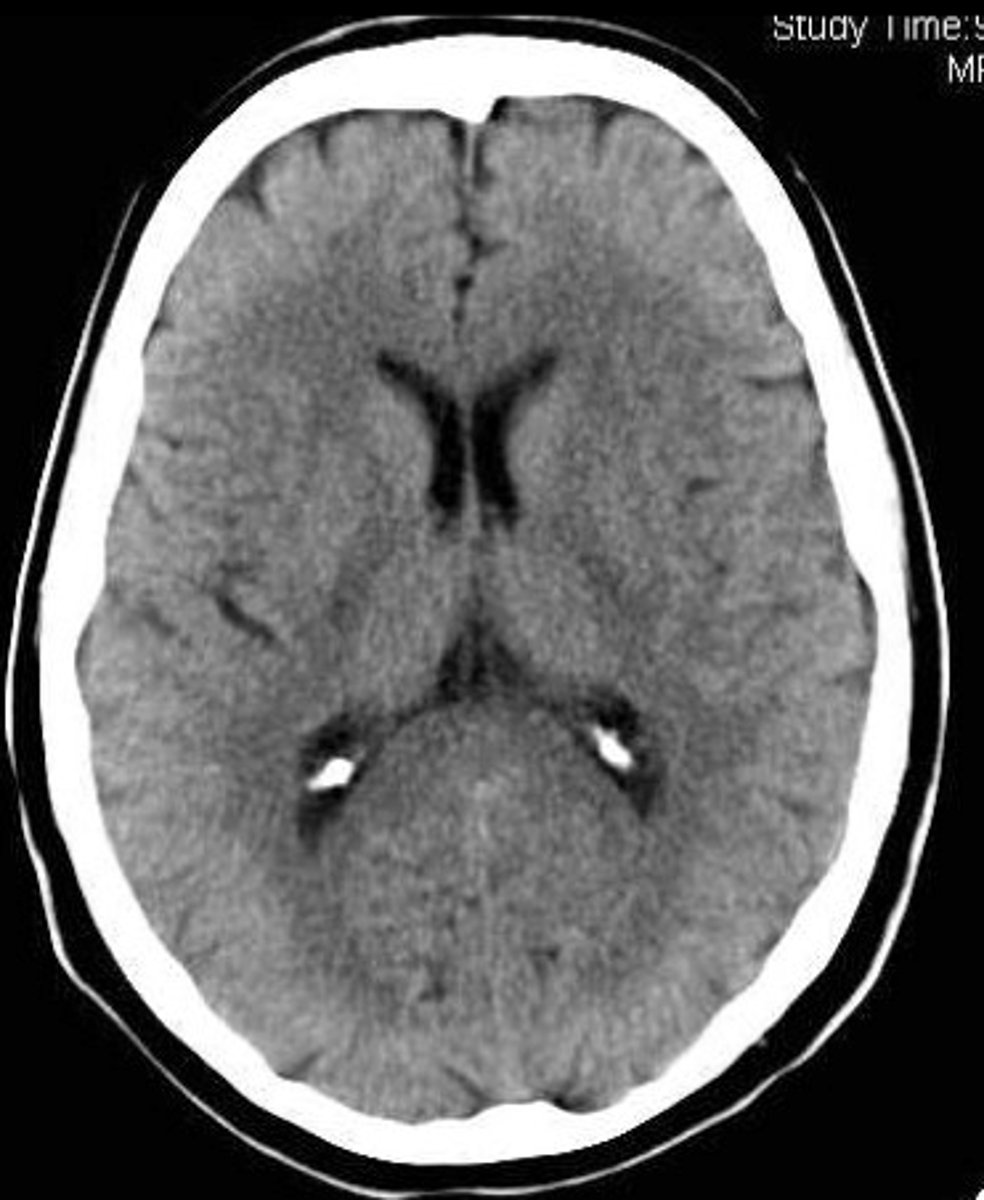

computed tomography (CT)

(CAT scan) a scanning technique using multiple X-rays to construct three-dimensional images